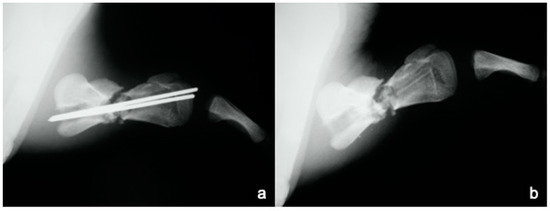

A juvenile sea turtle was presented to the Sea Turtle Clinic (STC) of Veterinary Medicine Department of the University of Bari with an entanglement lesion affecting the right front flipper. On admission, the sea turtle was measured and underwent a complete physical examination; curved carapace length (CCL) from notch to tip ranged 41 cm, curved carapace width (CCW) was 37 cm, and the weight was 18 Kg. The turtle appeared responsive but weak and dehydrated. Clinical evaluation of the musculoskeletal system performed out of the water showed swelling of the right front flipper and evidence of pain on deep palpation of the respective brachial muscle. A reduction in the right front flipper’s range of motion was observed when the turtle was examined in the water. Radiographic assessment, in dorso-ventral (D-V) and Caudo-Cranial (C-C) projections, indicated detachment of the distal epiphysis of the humerus, compatible with a type II Salter-Harris fracture, together with a transverse diaphyseal fracture (Figure 1). The turtle underwent general anesthesia, and the craniodorsal access to the humeral diaphysis was performed. The epiphyseal fracture was reduced by closed surgery and fixed using two crossed 2.5 mm Kirschner pins, introduced backward from the distal stump and brought out through the hyperflexed humerus-radio-ulnar joint. The same pins used to fix the epiphyseal fracture were inserted into the proximal stump to fix the diaphyseal fracture. After checking the stability of the fractures reductions, the surgically sectioned soft tissues were reconstructed, and post-operative radiographs were performed. Follow-up was performed after the surgery at 2, 4, 12, 16, and 24 months, when the turtle was released at sea. Three months after its release at sea, the turtle was caught dead in a fishing net at a depth of 40 m. To determine the evolution of bone repair from turtle release to death, the right humerus was removed for histological and histomorphometry analyses. Immediately after explant, the humerus was fixed in 4% buffered paraformaldehyde, dehydrated in ethanol, and embedded in methylmetacrylate. Serial cross sections, 750 µm thick, were cut at both the diaphyseal and epiphyseal fracture gaps using a circular diamond-bladed saw (Gillings Hamco) and were ground to a thickness of 100 µm. Sections were placed on a specimen holder and microradiographed using a microradiograph (Constant 1-K, Ital Structures, Italy) at a prefixed distance from the X- ray generator of 9.5 cm. X-ray exposure was set up at 8 kV and 14 mA. Contact microradiographs were obtained on Kodak high-resolution film (SO 343, Eastman Kodak Co., Rochester, NY, USA), developed with Kodak HC-110, fixed in Kodak UNIFIX, washed in distilled water and then airdried at room temperature. Sections were subsequently stained with 1% toluidine blue (pH 3.7) for mineralized tissue. Four separate levels were selected, three belonging to the mid-diaphyseal fracture gap, and one level to the epiphyseal fracture gap: the first and the fourth levels corresponded to the proximal and distal part of the callus, respectively, and the second and third levels to the center of the fracture (Figure 2). As a control, the left humerus, which had never been fractured, was processed with the same procedure. On the stained sections, using a Nikon DS-5 camera connected to a stereomicroscope (SMZ800, Nikon Europe B.V., Amstelveen, The Netherlands) and a DS camera control unit, the callus extension was measured and the amount of new laid down bone, cartilage, and fibrous tissue, expressed as percentage ratio of the entire section, were evaluated. Histomorphometry was performed using Nis-Elements BR analysis software (Nikon Europe B.V.).

The post-operative radiographic examination confirmed the correct reduction of the diaphyseal fracture, bone realignment, and the good fixation of the detached distal epiphyseal stump (Figure 3). Fifty days later, the X-ray follow-up showed persistent stability of the joint and bone sclerosis, near the diaphyseal fracture site. After 70 days, the turtle could swim and move around comfortably; radiographic examination showed a better filling of the diaphyseal fracture line and almost complete repair of the epiphysis (Figure 4). Four months after surgery, the animal was in good general condition and had recovered the right front flipper’s normal function. Radiography showed a complete repair of the epiphyseal fracture and remodeling of the normal bone architecture, while the diaphyseal fracture still lacked unifying bone callus tissue (Figure 5). After one year, the flipper showed complete clinical recovery without signs of pain, and radiologically the fracture site was fixed, showing signs of remodeling of the fracture stumps, areas of thickened fibrous tissue, but still no appreciable unifying bone callus (Figure 6a). The good positioning and tightness of the means of fixation were radiologically confirmed, but the surrounding bone reabsorption and decalcification processes were evident. Removal of the intramedullary pins was deemed necessary. Radiograms performed after removal of the pins showed the presence of calcified sites within the tissue interposed between the two bone stumps (Figure 6b). Two years after the procedure, radiographic follow-up demonstrated a better filling of the fracture line and further remodeling of the stump margins (Figure 7).

Figure 3. Caudocranial radiograph of the anterior right flipper: postoperative follow up examination.

Animals 13 00376 g003

Figure 4. Two-month follow-up performed in caudocranial view of the anterior right flipper showing the filling of the diaphyseal fracture line.

Animals 13 00376 g004

Figure 5. Postoperative checkup at four month: Caudocranial view of the anterior right flipper showed a complete repair of the epiphyseal fracture while the diaphyseal fracture still lacked unifying callus tissue.

Animals 13 00376 g005

Figure 6. Radiographic examination at 12 months before (a) and after (b) removal of the synthesis methods (Caudocranial view): remodeling of fracture stumps, areas of thickened fibrous tissue, but still no appreciable unifying callus.

Animals 13 00376 g006

Figure 7. Twenty-four-month follow-up (caudocranial view) demonstrating a better filling of the fracture line and further remodeling of the stump margins.